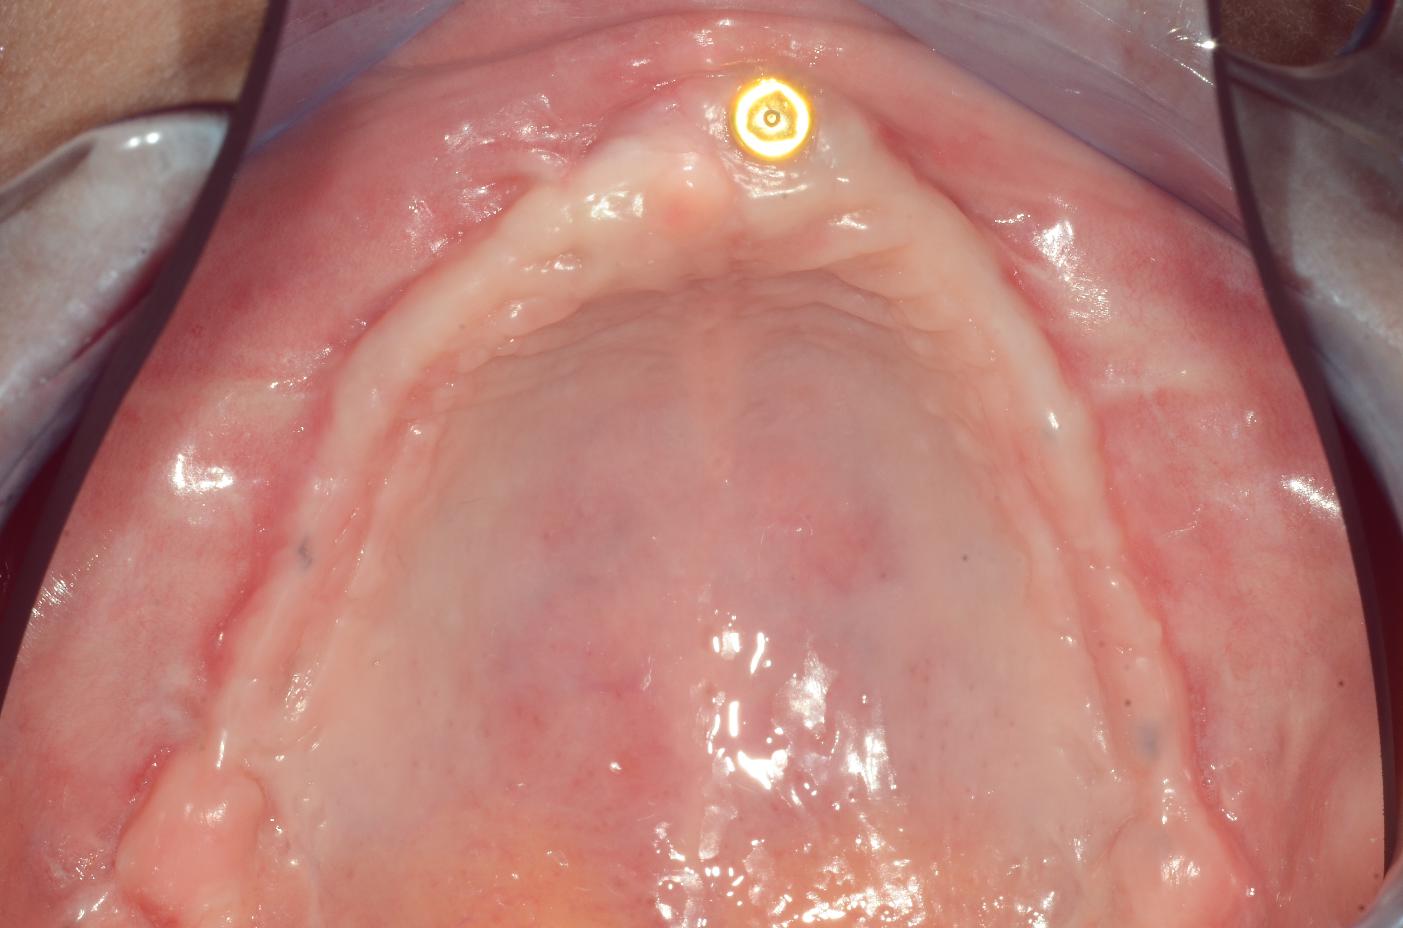

1/8 - Insufficient keratinized mucosa and extremely shallow vestibule on the maxillamucoderm® for full arch reconstruction of insufficient vestibular depth and lack of keratinized tissues - Dr. B. Mólnar & Prof. P. Windisch

Insufficient keratinized mucosa and extremely shallow vestibule on the maxilla